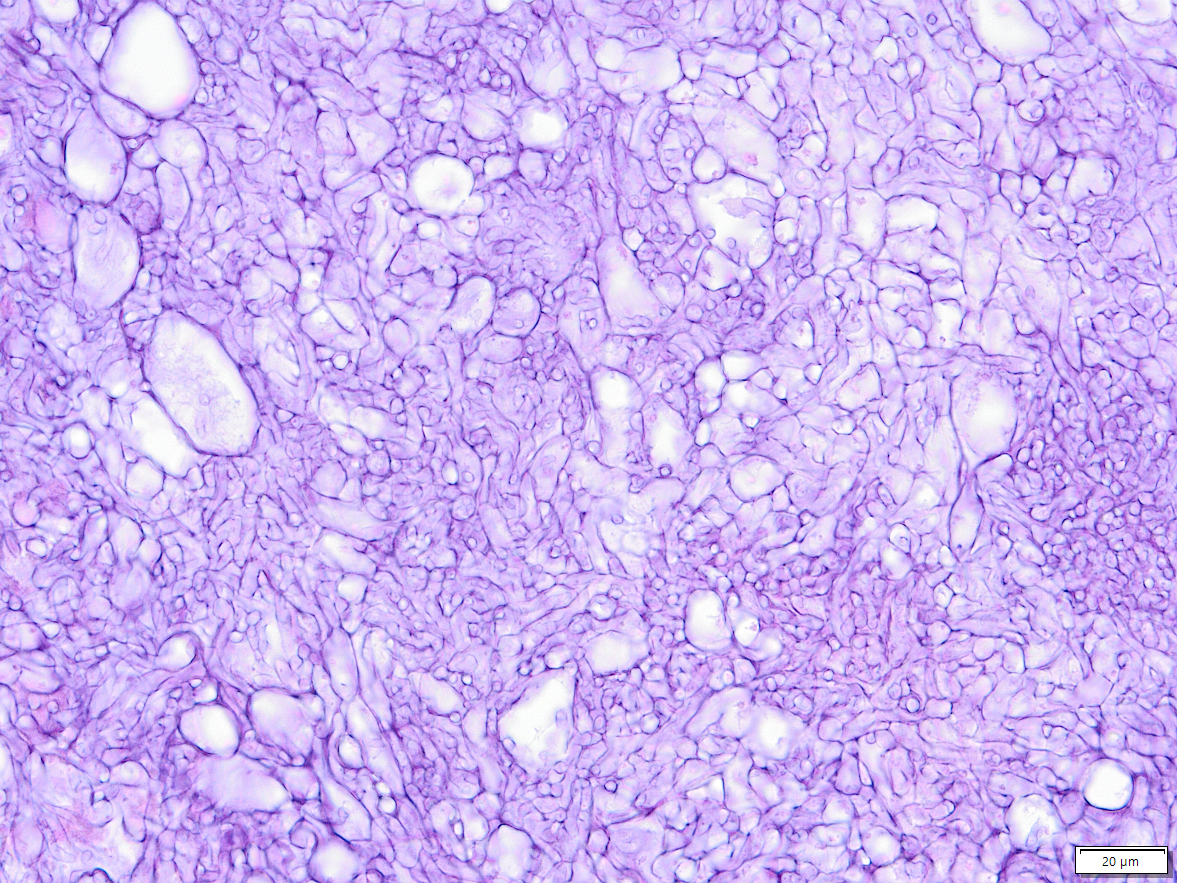

Ein Aspergillom ist gekennzeichnet durch (zunächst) nicht invasives Wachstum der Pilze. Hier in einem erweiterten Atemweg. Durch den dauernden Entzündungsreiz kommt es zu einer destruktion der lunge (im Bereich links ist nur noch Narbe, oben ist Emphysem, die Alveolarsepten "Lungenbläschen" sind also schon ziemlich kaputt).

1. Übersichtsbild. 1/4 der aufgeweiteten Bronchiektase (Erweiterter Atemweg) mit umliegender vernarbter Lunge